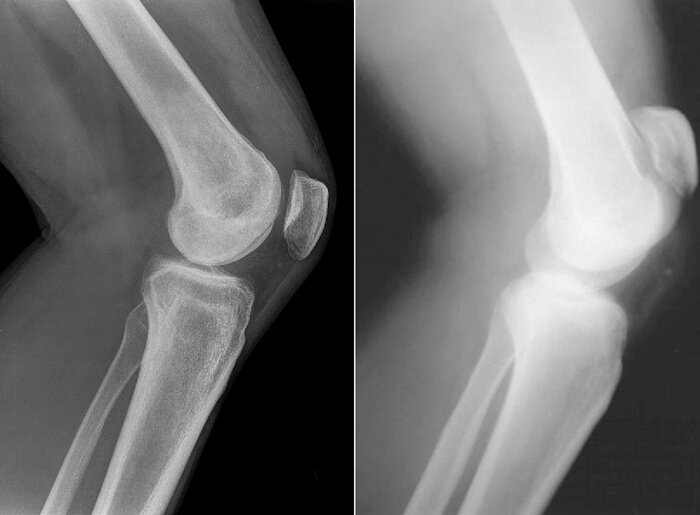

Травма надколенника: признаки и принципы лечения Ушиб или перелом надколенника (или коленной чашечки) – довольно частая травма у детей, активной молодежи и спортсменов. Основная роль коленной чашечки заключается в усилении разгибательной функции четырехглавой бедренной мышцы. Травмы коленной чашечки сопровождаются разными неприятными симптомами и существенно ограничивают подвижность пострадавшего. Обязательно надо показаться травматологу или хирургу. Травма нуждается в лечении и наблюдении у специалиста, т. к. при отсутствии адекватной терапии, пострадавший рискует получить осложнения и утратить природную подвижность коленного сустава. Признаки травмы надколенника: В зависимости от локализации переломы подразделяют на следующие виды: Горизонтальный – коленная чашечка раскалывается на две части. Вертикальный. Этот вид перелома встречается чаще всего. Похож на продольный, но линия разлома вертикальная. Краевой – фиксируют в том случае, когда от стенки кости отделяется небольшой фрагмент.

В зависимости от локализации переломы подразделяют на следующие виды:

Горизонтальный – коленная чашечка раскалывается на две части.

Вертикальный. Этот вид перелома встречается чаще всего. Похож на продольный, но линия разлома вертикальная.

Краевой – фиксируют в том случае, когда от стенки кости отделяется небольшой фрагмент.

Оскольчатый перелом – для него характерно образование трех и более осколков. Он самый опасный и сложный, т. к. отдельные костные фрагменты способны повредить сухожилия или мышцы.

Подбор лечения, которое основывается на результатах рентгенографии, компьютерной томографии или МРТ. Травматолог определяет характер повреждений надколенника, выявляет наличие смещения костных отломков и их величину, а затем принимает решение о методе лечения: консервативная терапия или операция.